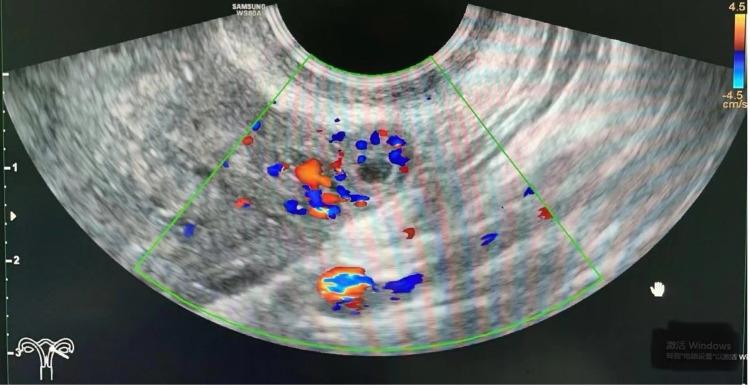

A 30-year-old gravida 1 para 0 woman with a history of left adnexectomy, due to left ovarian torsion 13 years ago, was referred to our hospital. She had experienced lower abdominal pain for 1 day and amenorrhea for 1 week. Transvaginal ultrasonography did not reveal an intrauterine pregnancy, but showed a suspected extrauterine gestational sac on the left adnexal area. The patient was diagnosed with ectopic pregnancy, and laparoscopy was performed. During the operation, we found a gestational sac on the left fallopian tube stump.

一名30岁、孕1产0的女性,13年前因左侧卵巢扭转行左侧附件切除术,现转诊至我院。她下腹痛1天,停经1周。经阴道超声检查未发现宫内妊娠,但在左侧附件区显示可疑宫外妊娠囊。患者被诊断为异位妊娠,并接受了腹腔镜检查。手术中,我们在左侧输卵管残端发现一个妊娠囊。